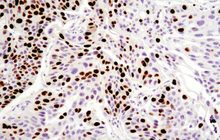

- General and specialized tissue and cell staining

- Immunocytochemistry (ICC) technique

- Immunohistochemistry (IHC) technique

Histological methods includes sample processing in the pathology laboratory, preparation of the slide and its examination under a microscope, sample fixation, molding, microtome cutting, staining and assembly of the slides.